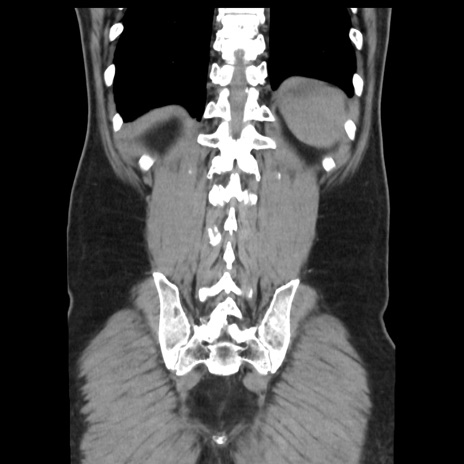

症例16(冠状断像)

【症例】 70歳代男性

【現病歴】 約1ヶ月前より間欠的に腹痛と嘔吐あり、当院消化器内科を受診したところCTで多発する肝臓のLDAを指摘され、精査中であった。以降は消化器症状は安定していたが、2日前より嘔気と腹痛があり、同日より排便・排ガスが消失した。改善認めず、 本日、救急外来を受診した。